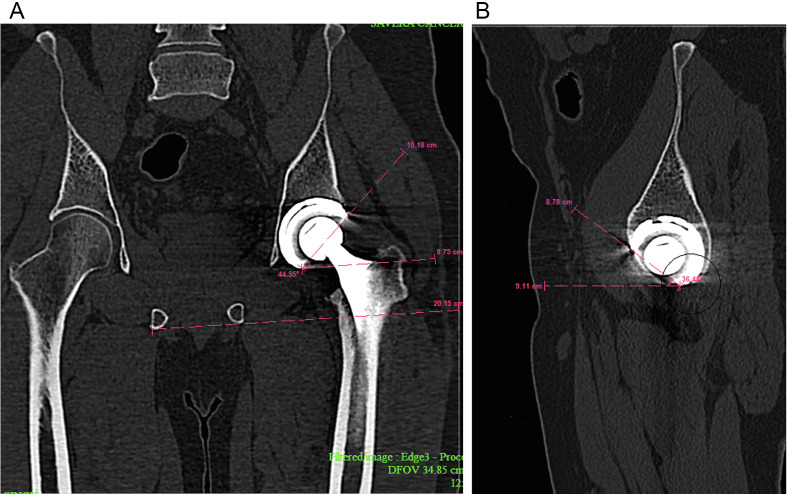

Introduction: Robot-assisted instrumentation during total hip arthroplasty (THA) has the potential to improve acetabular cup positioning. This study aimed to evaluate the precision of robotic-arm-assisted THA (rTHA) and assess whether the system can provide accurate cup positioning comparable to conventional THA (cTHA).

Methods: A single-center prospective cohort study consisting of 151 patients who underwent THA (108 rTHA and 43 cTHA). The robotically assisted system was used to match the postoperative computed tomography (CT) image of the pelvis with the planned and intraoperative anatomical landmarks. The cTHA cohort underwent hip replacement using the standard manual procedure, with acetabular component locations assessed during and after surgery.

Results: The rTHA cohort was significantly younger, but no other significant differences were found between the two cohorts in preoperative baseline data. In rTHA cohort, the planned inclination (40.0 ± 0.3°) closely matched the intraoperative (40.2 ± 2.7°; p = 0.54) and postoperative (40.7 ± 4.0°; p = 0.07) measurements. However, anteversion showed a significant increase from planned (19.4 ± 1.5°) to postoperative CT scan (28.7 ± 7.0°; p < 0.001). There was evidence of proportional bias in the measurements (p < 0.001). In the cTHA cohort, the mean inclination (43.1 ± 5.1°) did not show any significant change between the preoperative plans and postoperative assessments (p = 0.12); however, there was a remarkable change in the mean anteversion (17.6 ± 6.4°) between postoperative measurements and the preoperative plans (p < 0.001). The average anteversion in the preoperative plans did not differ remarkably between the rTHA and cTHA cohorts. However, the average inclination was substantially different between the two cohorts (p < 0.001). Both groups had no significant differences in the proportion of cups outside the referenced safe zones.

Conclusion: The results suggest that while robotic-assisted guidance ensures consistent cup inclination, there may be more variability in achieving the planned anteversion, which warrants further investigation into the factors influencing postoperative changes in acetabular orientation.